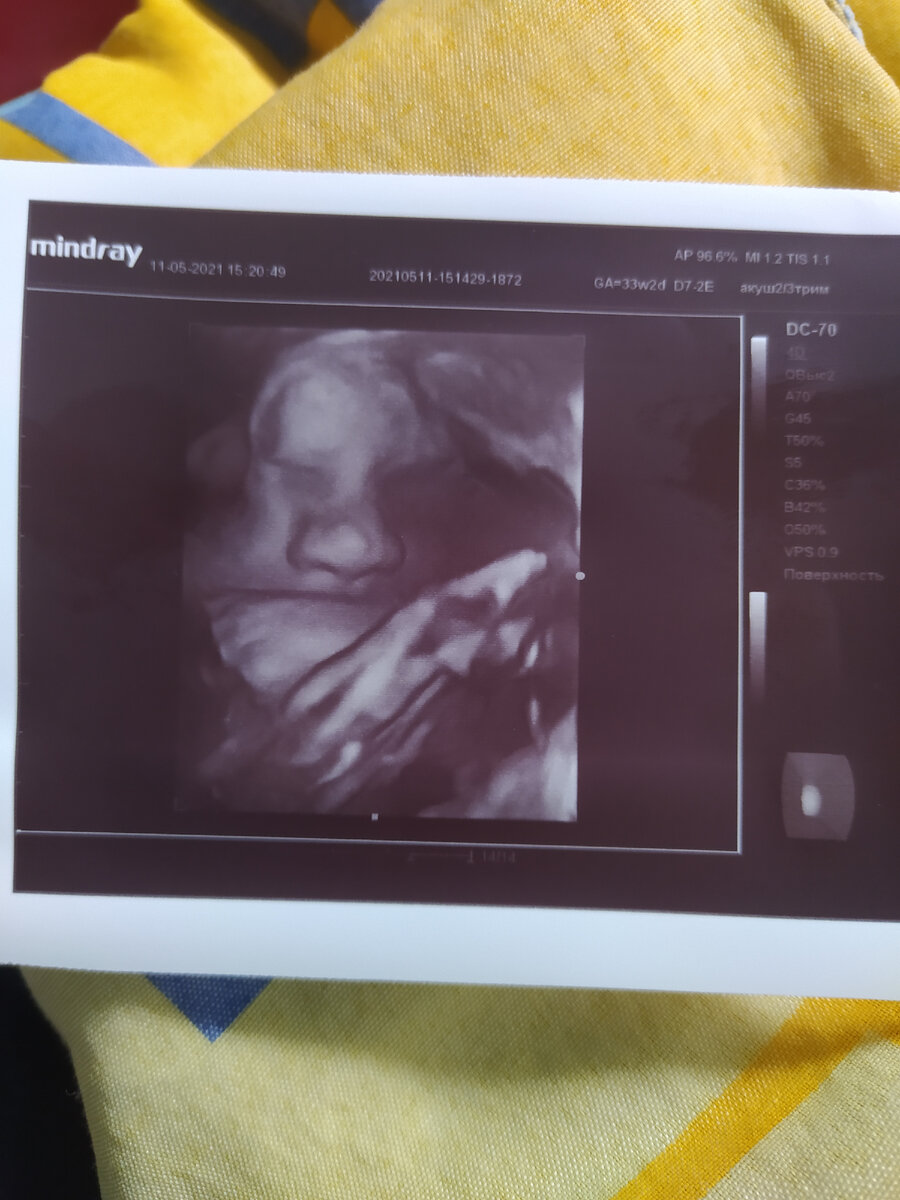

Фото из личного архива автора

Как итог - идеальная, как по учебнику, беременность, минимальный набор веса, абсолютно здоровый ребёнок и я , восстановившаяся после родов спустя три недели.